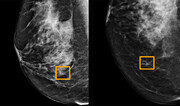

암은 생존율이 여전히 낮은 질병이다. 보건복지부 ‘국가암등록통계’에 따르면 2013∼2017년 암 진단을 받은 환자가 암에 걸리지 않은 사람과 비교해 5년 뒤 살아있을 가능성(상대생존율)은 70.4%다. 1993∼1995년에 42.9%이던 것과 비교하면 많이 올라갔지만 여전히 10명 중 3명이 5년 내 목숨을 잃는 셈이다. 과학자와 의사들은 암 생존율을 더 높이려면 조기 진단과 함께 치료 이후 예후 관리가 중요하다고 입을 모은다. 최근에는 인공지능(AI)이 암의 징후를 조기에 파악하고 치료 후 경과까지 철저히 감시하는 암 진단이 본격화하고 있다. 이미 일부 진료과목에선 AI가 전문의보다 암 조기 진단 정확도가 더 높다. 구글이 가장 앞서나가고 있다. 구글 헬스의 스콧 마이어 매키니 연구원 연구팀은 “AI가 유방암 조기 진단 정확도에서 방사선 전문의를 능가했다”는 연구결과를 국제학술지 ‘네이처’ 1일자에 발표했다. 이번 연구에는 영국 임페리얼칼리지런던 연구진과 알파고를 개발한 딥마인드, 미국 노스웨스턴대도 참여했다. 연구팀은 AI에 미국 여성 3097명과 영국 여성 2만5856명의 유방암 진단 영상을 학습하도록 했다. 그런 다음 AI와 방사선 전문의 6명에게 처음 보는 X선 영상 500장을 제시하고 유방암 여부를 판단하게 했다. AI의 오진율은 전문의보다 낮았다. AI가 암이 아닌데 암이라고 판단한 비율은 전문의보다 영국 여성의 영상은 5.7%, 미국 여성은 1.2% 낮았다. 암에 걸렸는데 암이 아니라고 판단한 비율도 AI가 전문의보다 각각 9.4%와 2.7% 낮았다. 연구팀은 지난해 5월 AI가 폐암 진단에서 최고 94.4%의 정확도를 보였다는 연구 결과를 국제학술지 ‘네이처 메디신’에 발표했다. 이는 방사선 전문의보다 5∼11% 높은 정확도다. 연구팀은 당시 “AI가 4만2290개의 흉부 컴퓨터단층촬영(CT) 영상 자료를 학습하면서 전문의도 보지 못한 암의 패턴을 인식했다”고 설명했다. 독일 하이델베르크대 의대 연구팀이 지난해 개발한 AI의 피부암 조기 진단 정확도도 95%에 이른다는 결과도 나왔다. 최근에는 암 치료 이후 경과를 예측하는 방법에서 탁월한 성과도 나타나고 있다. 일본 이화학연구소(RIEKN·리켄) 고급지능프로젝트 야마모토 요이시로 연구원은 인간이 만든 전립샘암 예후 예측 기준보다 더 정확도가 높은 AI 예측 연구결과를 국제학술지 ‘네이처 커뮤니케이션’에 지난달 18일 공개했다. 연구팀은 AI에 일본의대병원(NMSH)이 지난 20년간 보유하고 있던 전립샘암 환자 1만3188장의 자료를 학습시켰다. 그 결과 지금까지 가장 정확하다는 예후 예측 기준인 ‘글리슨 점수’보다 더 정확한 예측 결과를 얻었다. 암의 예후 예측이 중요한 이유는 개인마다 재발과 전이 위험이 다르기 때문이다. 예후에 영향을 주는 요인은 암 세포의 크기, 분화, 형태, 나이, 성별 등 다양하다. 송교영 가톨릭대 의대 교수는 “같은 종류의 암이라도 사람에 따라 재발 확률이 달라질 수 있다”며 “개인에 맞는 치료를 위해선 예후 예측이 중요하다”고 설명했다. 서울대병원 강경훈·배정모 교수 연구팀도 AI로 대장암 조직 슬라이드를 분석해 재발 및 전이 위험이 2∼3배 높은 환자를 선별하는 방법을 개발했다. 배 교수는 “기존에 알려진 예후 인자들과 함께 진단에 활용하면 재발 위험성이 높은 대장암 환자를 더 잘 찾아내 치료할 수 있을 것”으로 보고 있다. 고재원 동아사이언스 기자 jawon1212@donga.com}